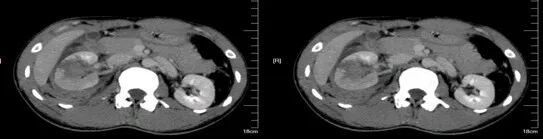

肾挫伤

肾挫伤是一种比较多见的肾损伤,肾组织损伤较轻,肾包膜和肾盂大多保持完整,肾实质内产生瘀血或血肿,并有少量血液流入肾盂导致血尿。肾挫伤在X线造影片上可不显示形态上的改变。一般均能自行愈合而不造成严重后果。